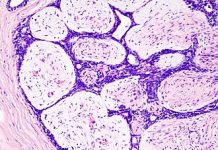

Ведущую роль в верификации диагноза и оценке тяжести процесса играет рентгенодиагностика, начинающаяся с обзорной рентгенографии брюшной полости. На снимках при остром воспалении визуализируется увеличение почки, нечеткость её контуров и исчезновение тени поясничной мышцы из-за отека клетчатки. Основным функциональным методом служит экскреторная урография, позволяющая оценить динамику выведения контраста. К рентгенологическим признакам острого процесса относятся замедление выделения вещества, ограничение подвижности почки при дыхании и спастическое сужение чашечек. При хроническом течении рентгенодиагностика выявляет деформацию чашечно-лоханочного комплекса, булавовидное расширение чашечек и симптом Ходсона — локальное истончение паренхимы. Лечение носит комплексный характер и базируется на назначении антибактериальных препаратов (цефалоспоринов или фторхинолонов) для подавления возбудителя. Обязательным условием является обеспечение оттока мочи, что контролируется рентгенологически при наличии препятствий. Скрининг пациентов с хронической формой направлен на выявление сморщивания почки через контрольные снимки. Профилактика заключается в устранении уродинамических нарушений и поддержании достаточного диуреза.